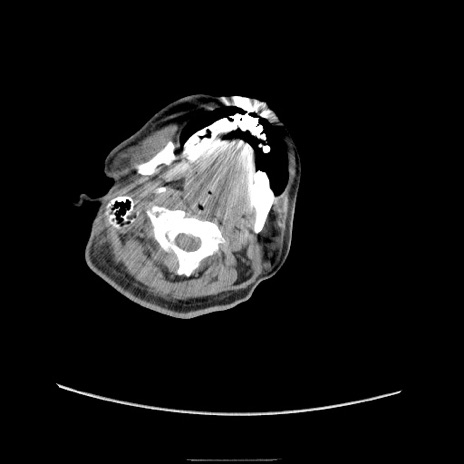

冠状断像